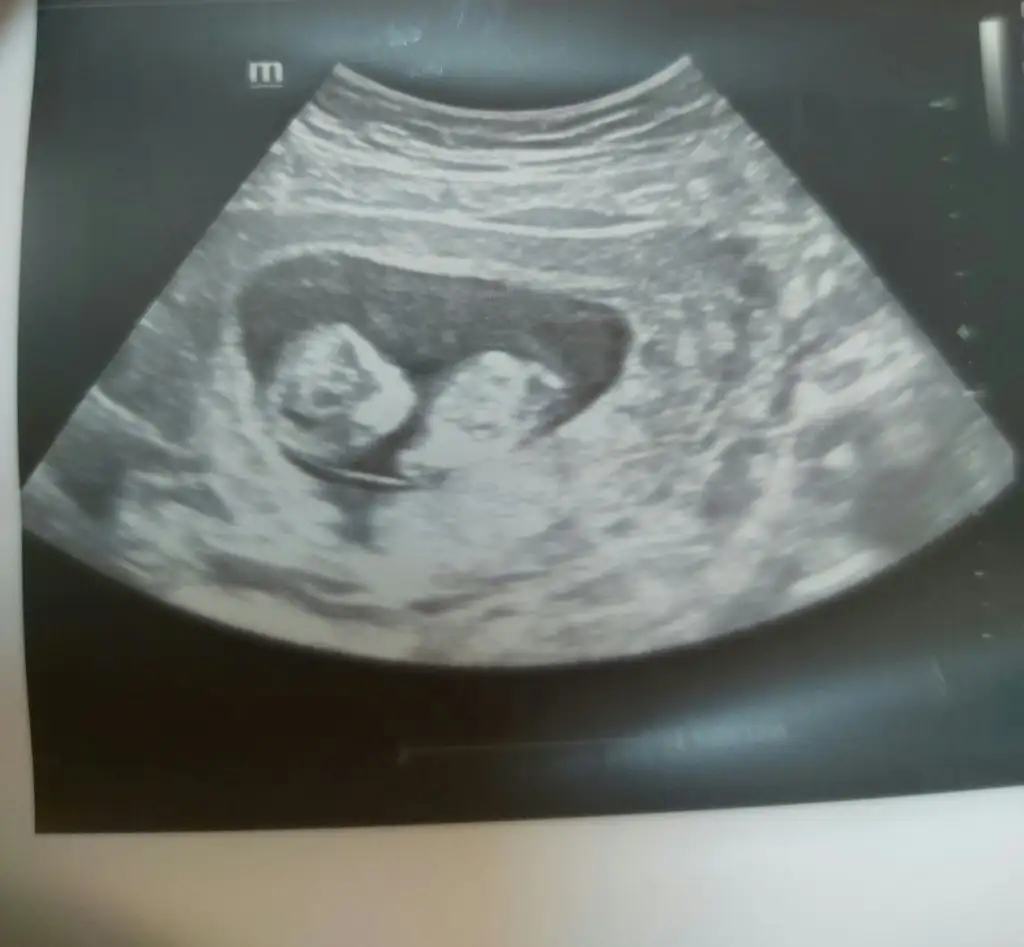

Bebeğimin cinsiyeti